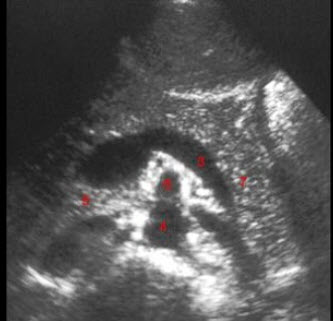

D.1000Hz

E.1MHz